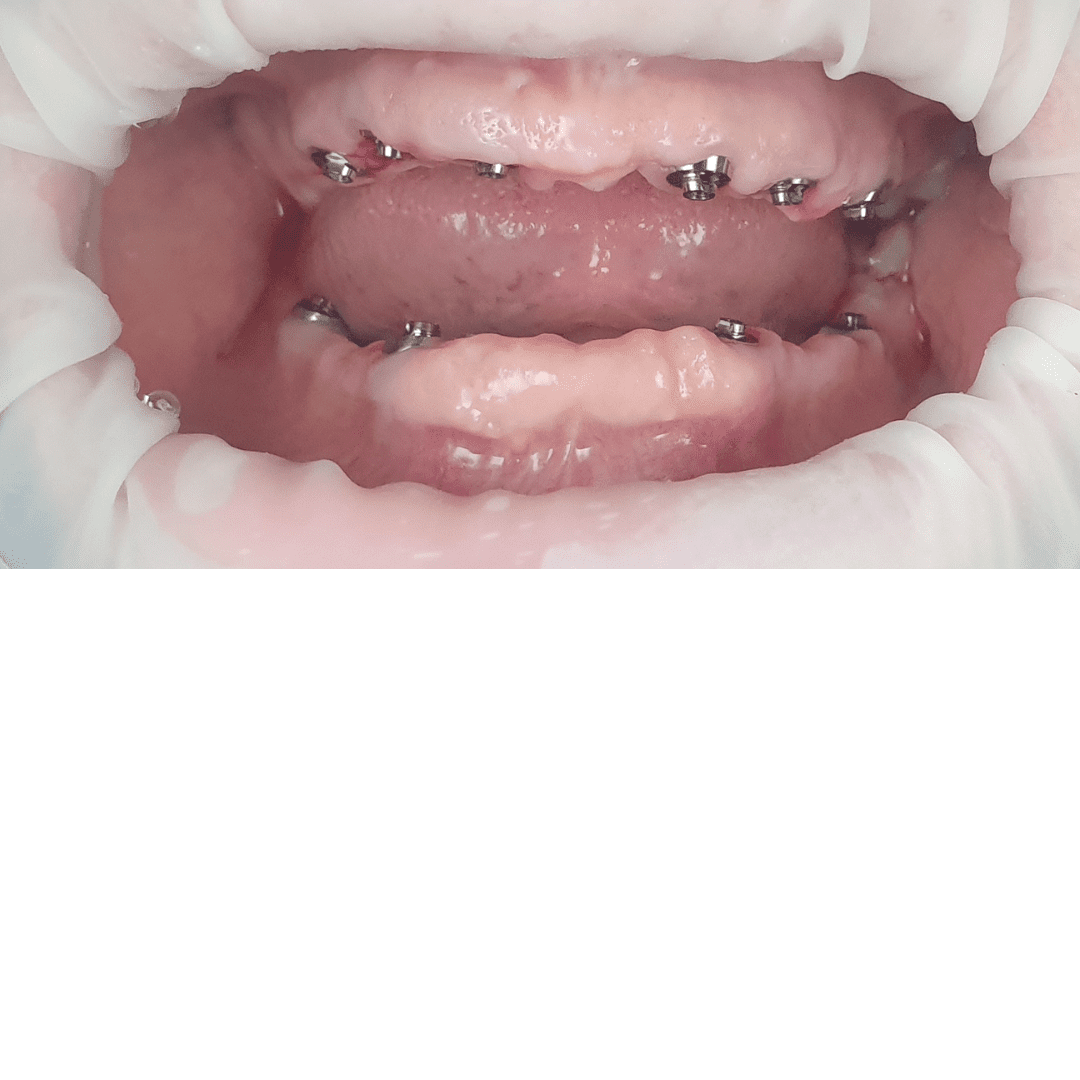

- Intervenția chirurgicală

- Aplicare lucrare provizorie pe implanturi